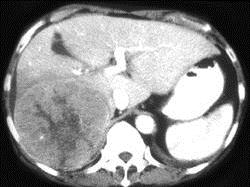

男,69岁,肝区疼痛,消瘦乏力三月余,CT检查如图,请作出最可能诊断 ( )A、肝转移瘤B、巨块型肝癌C、肝脓肿D、肝血管瘤E、肝囊肿

问题 男,69岁,肝区疼痛,消瘦乏力三月余,CT检查如图,请作出最可能诊断 ( )

选项 A、肝转移瘤 B、巨块型肝癌 C、肝脓肿 D、肝血管瘤 E、肝囊肿

答案 B